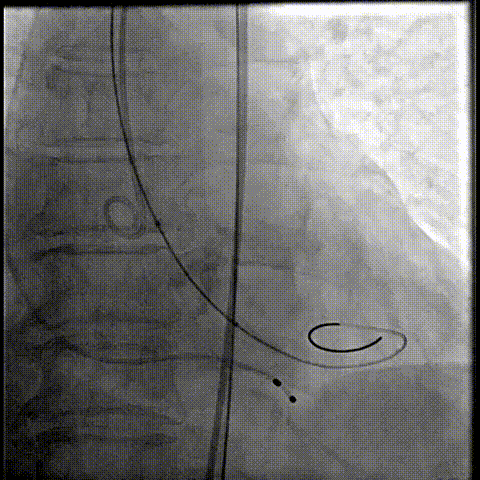

释放瓣膜

80%工作位评估

23球囊后扩

最终造影形态位置良好,轻微瓣周漏

术后压差降为0mmHg